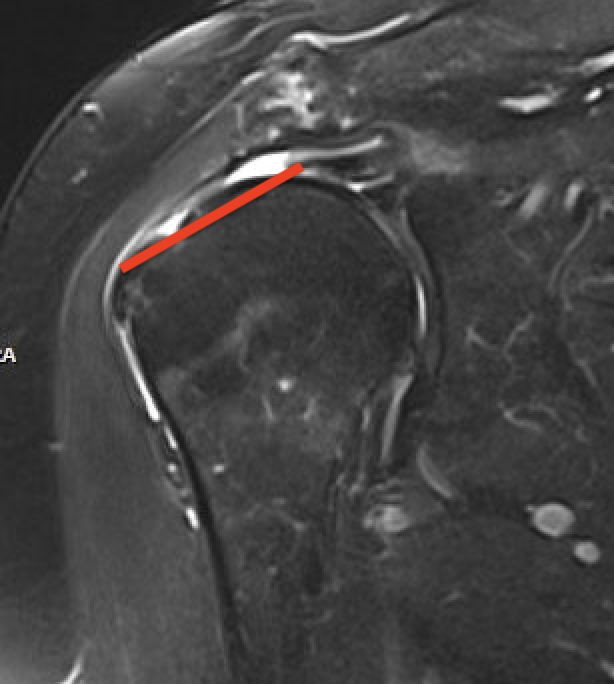

Small full thickness rotator cuff tear of supraspinatus - retracted to footprint

Large full thickness tear of supraspinatus and infraspinatus tendon - retracted to midhumeral head

Massive rotator cuff tear of the supraspinatus and infraspinatus tendon - retracted to glenoid

Supraspinatus atrophy

Tangent sign

- sagittal MRI

- line connecting superior coracoid and superior border scapular spine

- if supraspinatus muscle is below line, there is significant atrophy

- positive tangent sign / significant atrophy associated with larger tears / irrepairable tears

Negative tangent / no atrophy Positive tangent / significant supraspinatus atrophy